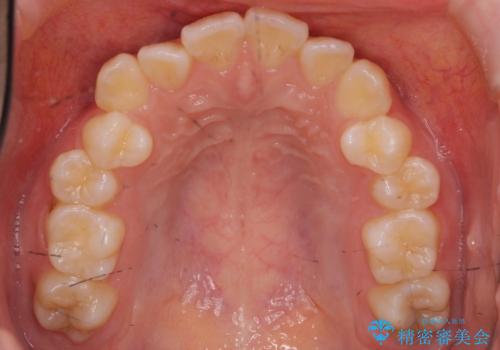

スペースを確保するために、歯をわずかに削る処置、奥歯を後ろに下げる処置(インプラント矯正)を行っています。